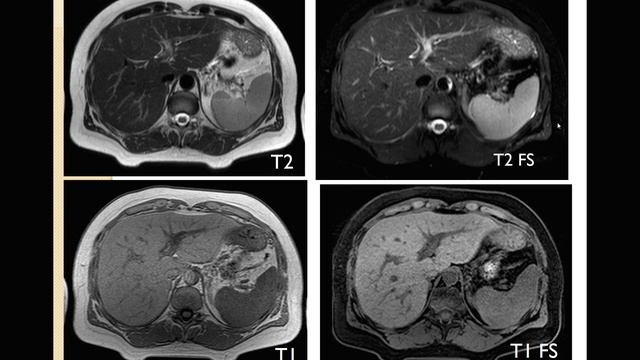

прямой эфир с Романом Вадимовичем Бартеневым @orthodoc.md - врачом ультразвуковой диагностики, ортопедом-травматологом, мануальным терапевтом, специалистом по скелетно-мышечной боли и физической реабилитации. Тема прямого эфира: «МРТ. Зачем это исследование?» Руководитель проекта - Касаткин М.С. @dr.kasatkin вместе с нашим гостем обсудит следующие вопросы: какой смысл МРТ в современном мире; нужно ли знать МРТ массажисту и тренеру; все ли врачи понимают МРТ; МИФЫ об МРТ. https://www.instagram.com/kineziocourse/ КИНЕЗИОТЕЙПИРОВАНИЕ ОБУЧЕНИЕ https://www.instagram.com/orthodoc.md/ Бартенев Роман Вадимович ОРТОПЕД, МАНУАЛЬНЫЙ ТЕРАПЕВТ https://kinesiocourse.getcourse.ru/mri ОНЛАЙН КУРС МРТ КОЛЕННОГО СУСТАВА